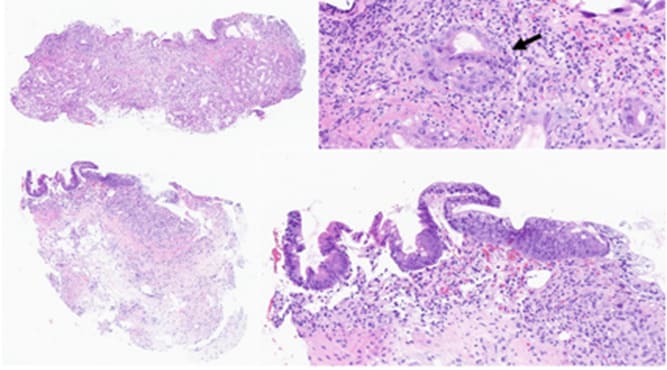

Figure 1: Histological findings. A and B (Hematoxylin&Eosin, H&E, x75 and x400), gastric biopsy at d+38. The gastric biopsy shows focal denudation, with major gland dystrophy and partial loss. Clustered apoptotic bodies are seen (arrow). C and D (H&E, x60 and x200), duodenal biopsy at D+23 (d+70). Partial re-epithelialization and regeneration of the duodenal mucosa is seen, with persisting gland loss

Eighteen days after the first MSC-FFM infusion (D+18), we observed a partial resolution with a decrease of gastrointestinal-aGvHD from grade IV to grade III, which was reflected in a decrease in blood transfusions and endoscopic clot removal. Endoscopic evaluation and histology performed on D+23 showed focal duodenal re-epithelialization, co-existing, however, with areas of ulceration on D+23 (Figure 1, C and B; Figure 2). The evolution continued to be favorable with a transient complete clinical remission on D+79 (Figure 3). The diarrhea and bleeding resolved completely. A persistent abdominal discomfort prevented a complete resumption of oral feeding and induced persistent need for parenteral nutrition. From D+97, during the attempt to start enteral nutrition, the patient’s digestive losses slightly increased, with values mostly consistent with a grade I GI-GvHD until the end of his life (Figure 3).